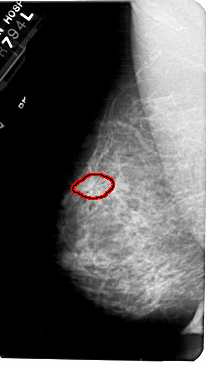

A_1777_1.LEFT_MLO

LEFT_MLO LINES 5491 PIXELS_PER_LINE 3106 BITS_PER_PIXEL 12 RESOLUTION 43.5 OVERLAY

FILE: A_1777_1.LEFT_MLO.OVERLAY

TOTAL_ABNORMALITIES 1

ABNORMALITY 1

LESION_TYPE MASS SHAPE ARCHITECTURAL_DISTORTION MARGINS ILL_DEFINED

ASSESSMENT 4

SUBTLETY 2

PATHOLOGY BENIGN

TOTAL_OUTLINES 1

BOUNDARY